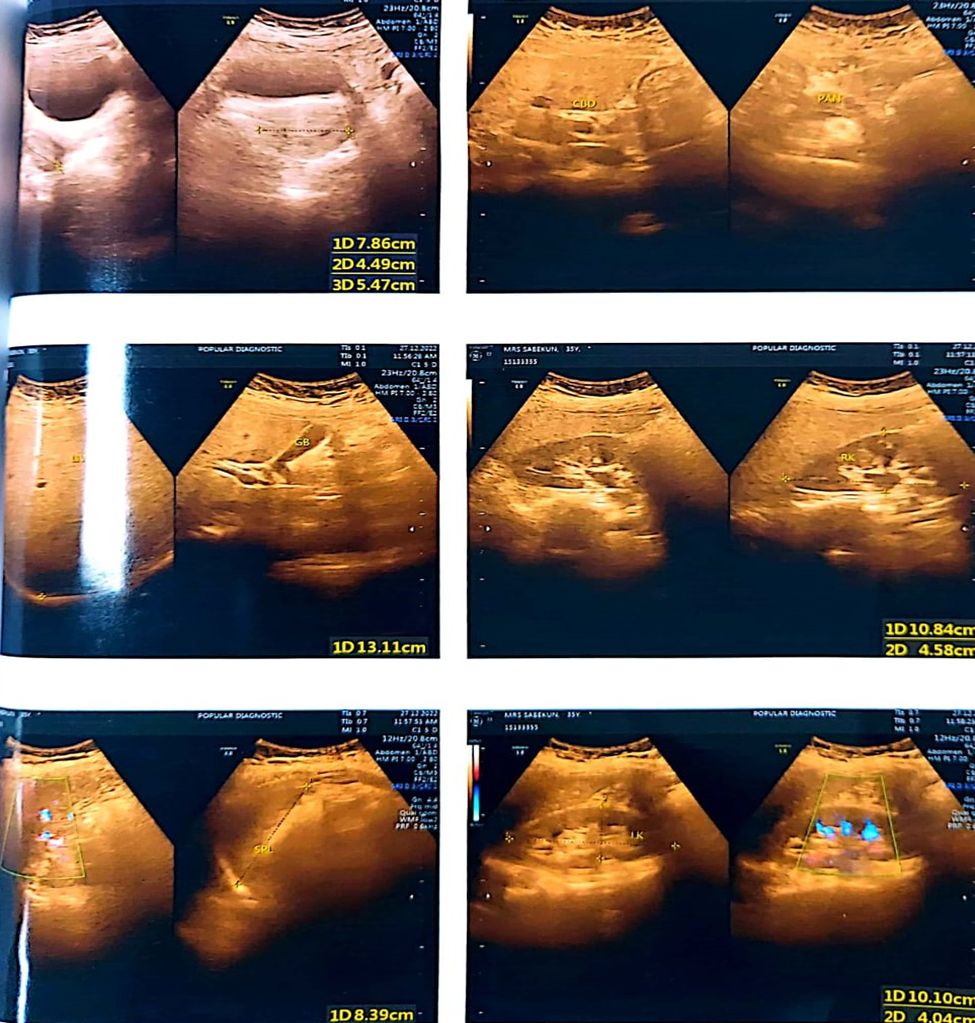

A 35-year-old married Bangladeshi lady noticed a painless lump in her right breast’s upper and inner quadrant 1 month ago. After the initial presentation, she underwent a breast examination and routine ultrasonography of both breasts. Ultrasound of the breast revealed a fairly large irregular complex mass measuring about (80 × 51mm, 04 mm from the skin).

Figure 1: Imaging of Metaplastic carcinoma